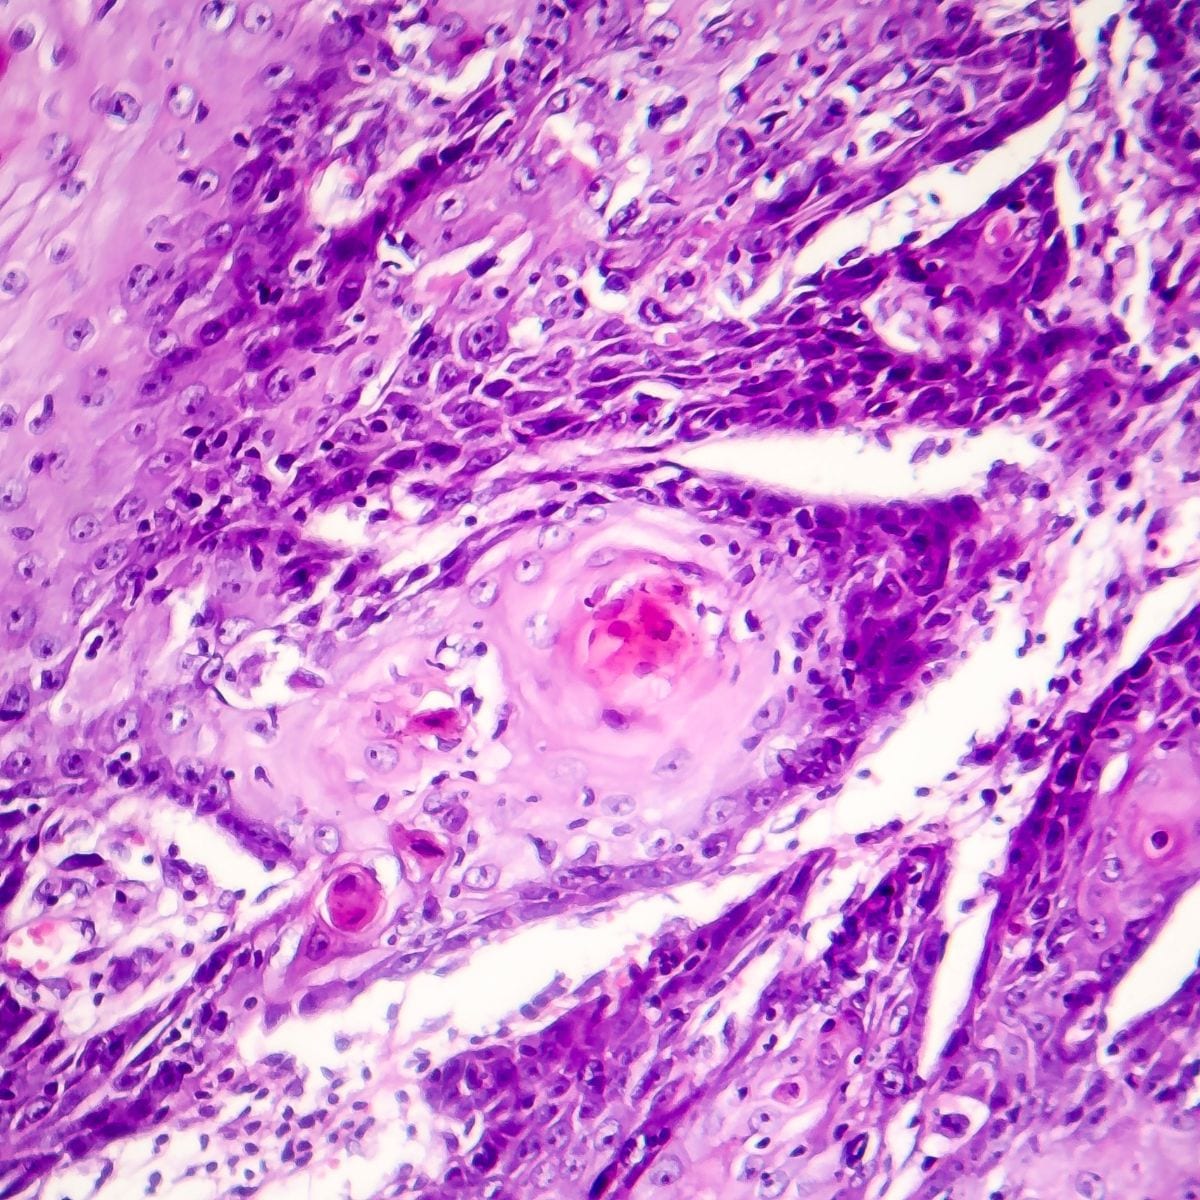

Il carcinoma spinocellulare (SCC), noto anche come spinalioma, è un tipo di carcinoma della pelle che origina dalle cellule squamose, le quali compongono la maggior parte degli strati superiori dell’epidermide. È il secondo tipo più comune di carcinoma della pelle, dopo il carcinoma basocellulare.

Aspetto Clinico: Si manifesta spesso come una lesione rossa, squamosa o crostosa che può ulcerarsi e sanguinare.